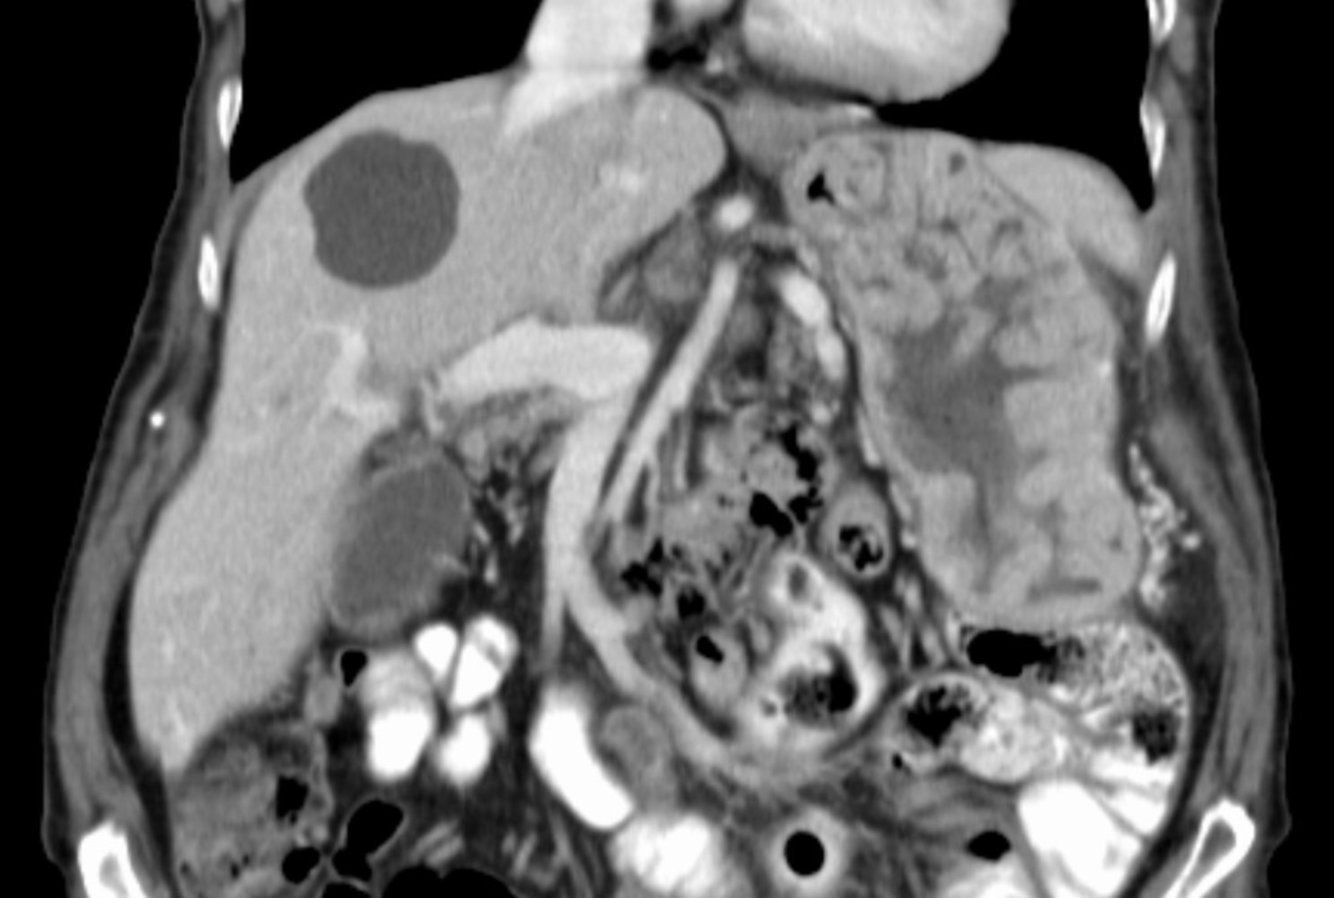

Gastrointestinal Stromal Tumor (GIST)